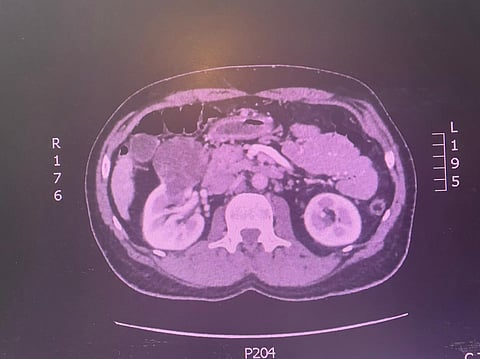

كان حجم الورم 8 سنتيمترات وبالقرب من أوردة وشرايين الكلية

تمكن فريق من قسم جراحة المسالك البولية في مستشفى الملك عبدالعزيز التخصصي بالطائف، من استئصال جزئي لورم نشأ بالكلية اليمنى لمريض خمسيني.

وكان حجم الورم 8 سم وبالقرب من أوردة وشرايين الكلية، وقد تم استئصال الورم وجزء بسيط من الكلية دون استئصال الكلية كاملةً، وهذه من الحالات المستحدثة بتخصصي الطائف وهي الحالة الخامسة.